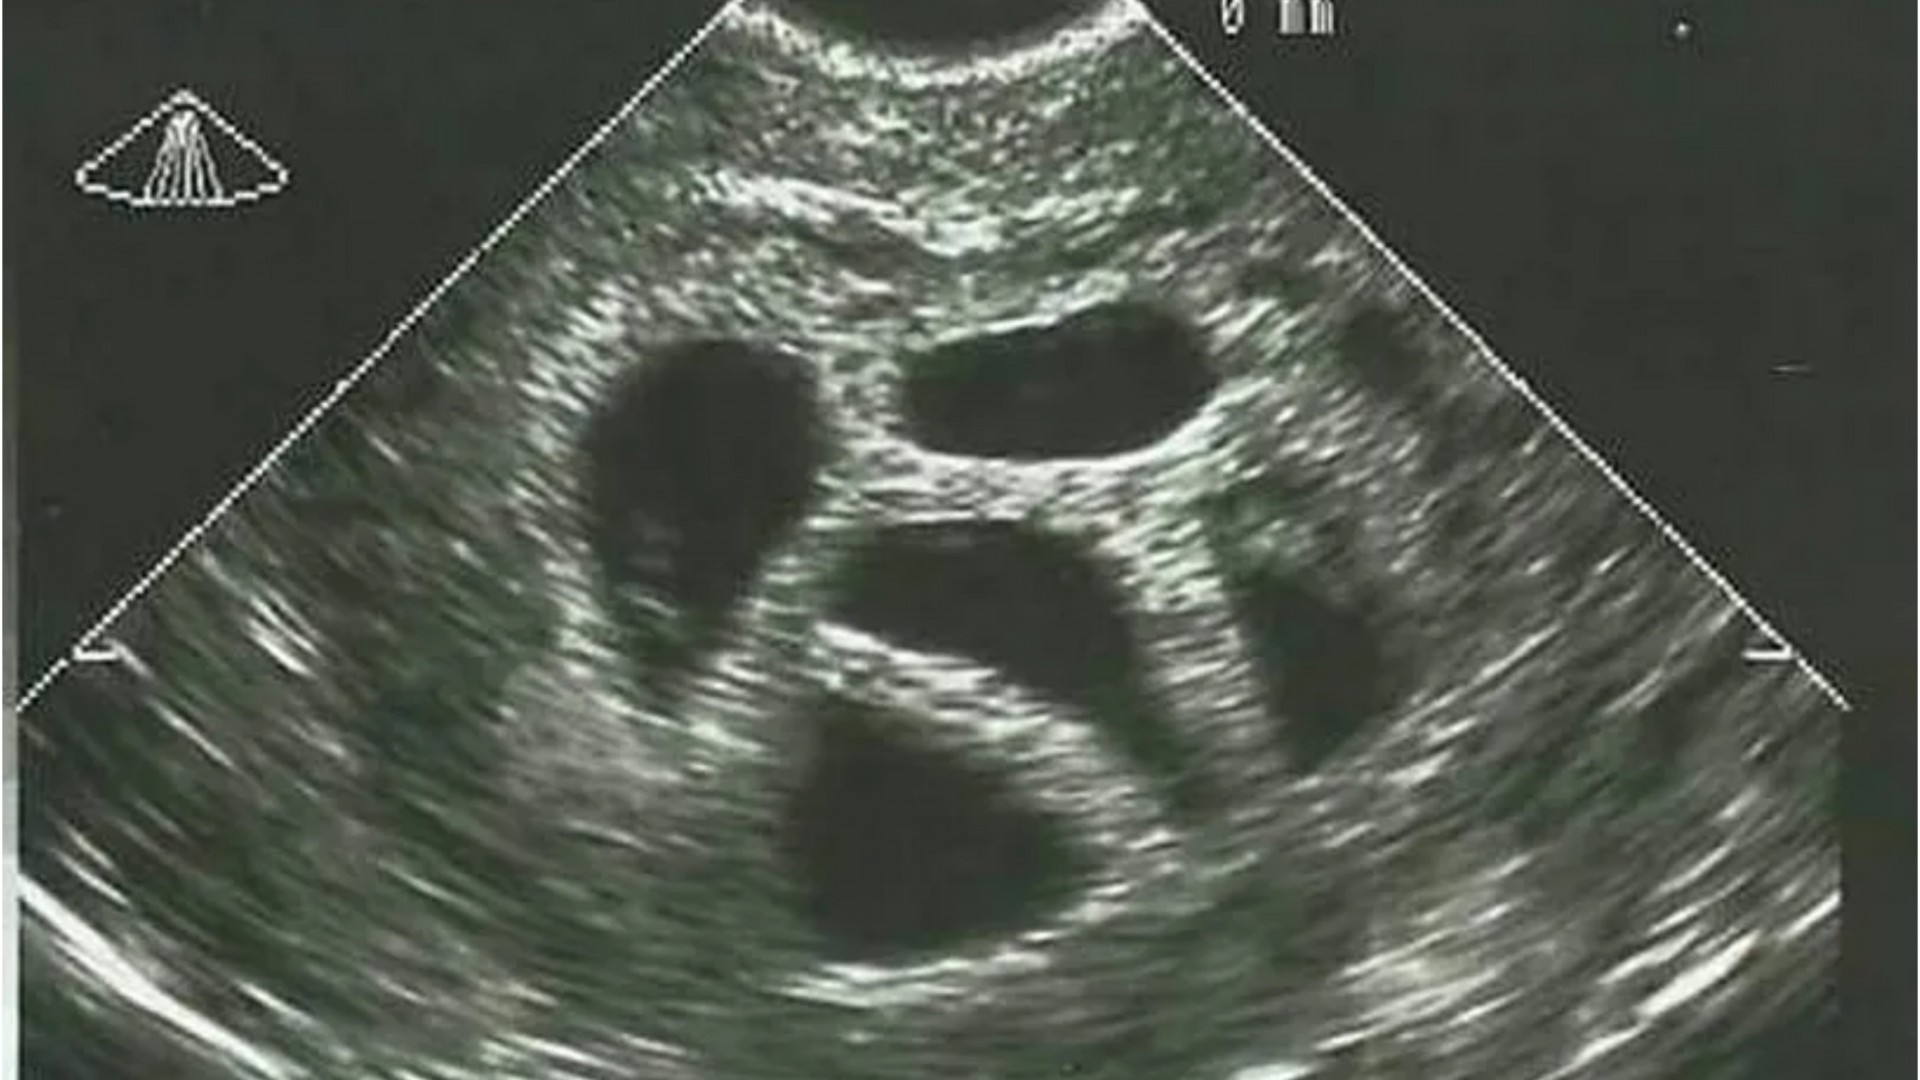

Доктор видел петорка на ултразвук, па ја советувал идната мајка да абортира: 20 години подоцна ја објави таа фотографија

Во свет каде што секоја одлука за животот се претвора во дебата, приказната за Американката Сузан Томпсон го враќа фокусот на она што е суштинско - верата, љубовта и храброста да се верува во невозможното. Таа имала само 28 години кога дознала дека носи петорка. Лекарите биле директни; ја советувале да направи селективен абортус, објаснувајќи дека бременоста е ризична и дека „не е реално“ сите деца да преживеат.